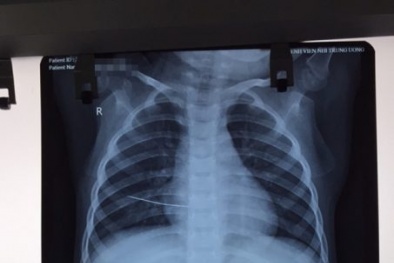

Nhiễm trùng, thủng tim vì trẻ ngã trúng vào kim khâu mẹ đánh rơi không biết

(VietQ.vn) - Bác sĩ cảnh báo kim khâu là vật nhọn nhỏ nên dễ dàng xuyên qua da vào cơ thể gây hại cho con người, đặc biệt gây hại cho trẻ nhỏ.